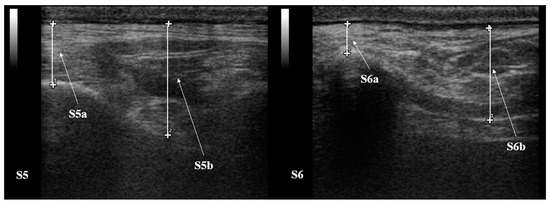

2.4. RTU Assessment of SF Thickness

| S5 (mm) | a | 10.25 ± 2.86 | 11.17 ± 3.19 | 10.70 ± 4.17 | 10.02 ± 3.37 | 9.17 ± 3.82 |

| b | 20.83 ± 13.51 | 20.18 ± 1.49 | 17.78 ± 4.30 | 21.15 ± 2.10 | 18.92 ± 4.58 | |

| S6 (mm) | a | 10.55 ± 3.12 | 8.53 ± 2.38 | 8.47 ± 3.00 | 6.25 ± 2.76 | 4.72 ± 2.60 |

| b | 20.28 ± 4.32 | 18.10 ± 2.42 | 20.17 ± 3.70 | 16.50 ± 3.56 | 17.58 ± 4.15 | |